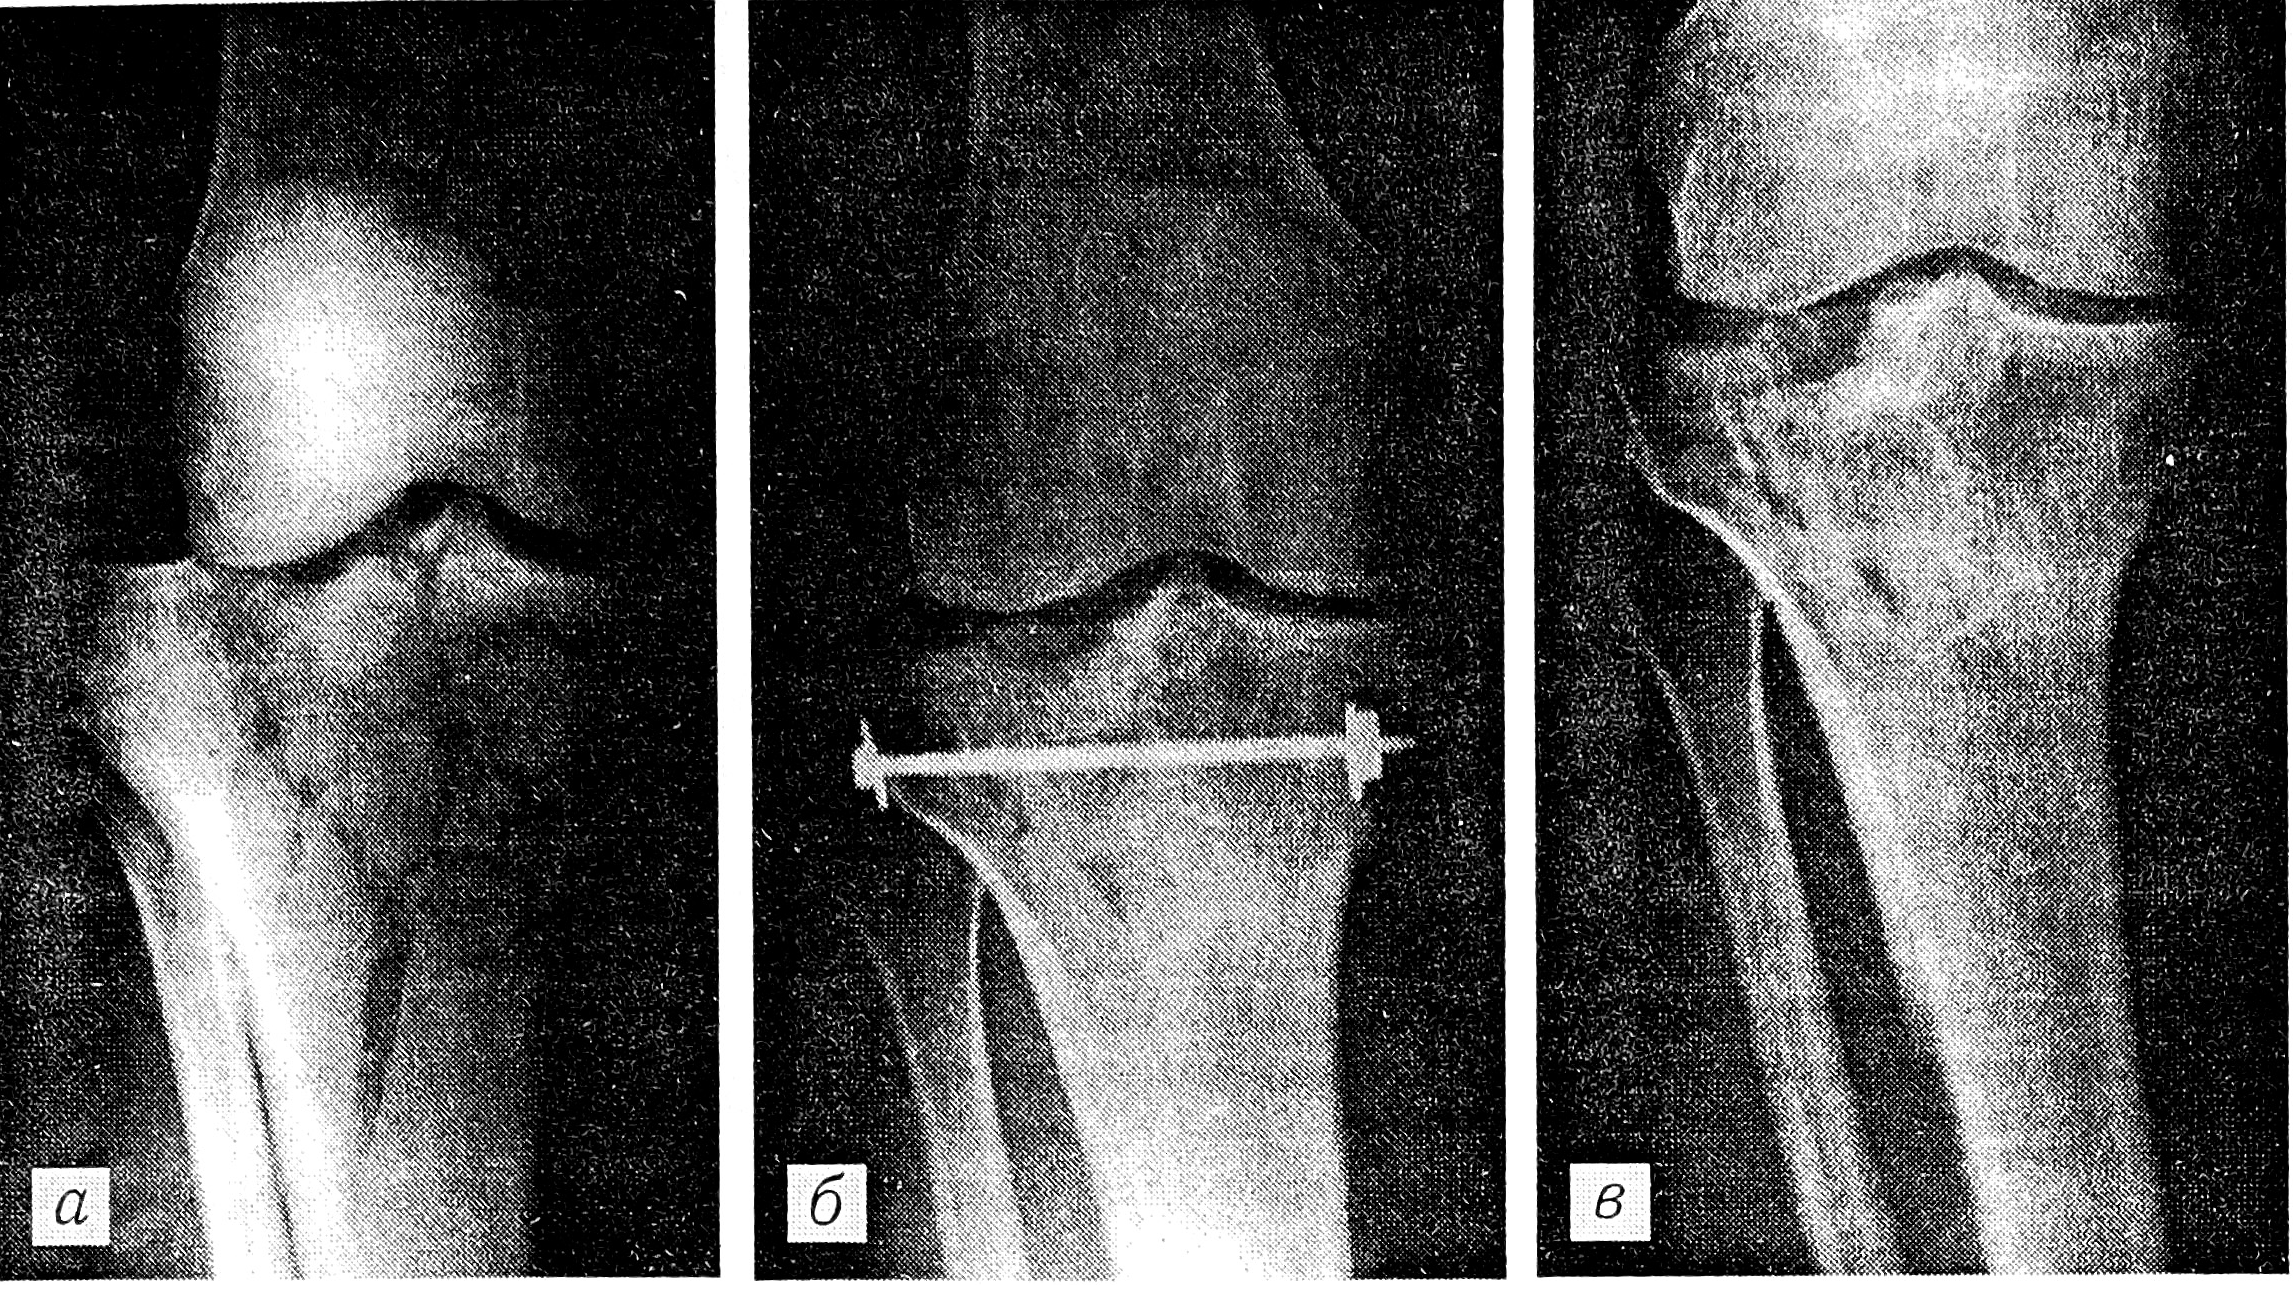

Механогенез перелома мыщелка с подвывихом или вывихом голени представляется следующим. При падении с высоты на выпрямленные ноги или падении на дороге от наезда автотранспорта происходит отведение голени кнаружи и увеличение физиологического вальгусного угла в коленном суставе. Острый край латерального мыщелка бедра воздействует с травмирующей силой, направленной кнутри и вниз, и откалывает медиальный мыщелок большеберцовой кости вместе с межмыщелковым возвышением. Латеральный мыщелок бедра внедряется в губчатую ткань эпиметафиза большеберцовой кости и смещает кнаружи ее латеральный мыщелок с диафизом (рис. 1). При этом крестообразные связки коленного сустава не повреждаются, так как линия перелома проходит через латеральный мыщелок большеберцовой кости перед местом их прикрепления к переднему и заднему межмыщелковому полю.

Рис. 1. Схема механизма перелома медиального мыщелка большеберцовой кости с вывихом.